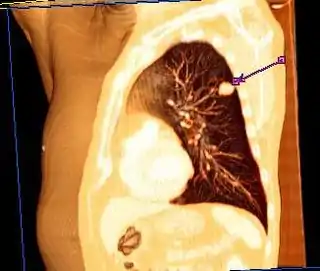

![]() Corte torácico en un estudio tomográfico mostrando la localización de un tumor de cáncer pulmonar. | ||

Tomografía axial computarizada

La tomografía axial computarizada es de gran utilidad en el cáncer de pulmón y se recomienda en todo paciente con un nódulo pulmonar solitario detectado por radiografía.[121] Algunas ventajas de una tomografía incluyen:

- Encuentra su principal aplicación en la determinación del grado de extensión de la neoplasia; tanto intratorácica como extratorácica, y de las adenopatías mediastínicas.[134]

- En la diferenciación entre nódulos benignos y malignos, además de la detección de pequeños nódulos con mayor nitidez que en las radiografías simples. Proporcionan valiosa información sobre la existencia de cavitación, calcificación y en ocasiones la localización intrabronquial del tumor, en fin, de las características morfológicas del tumor.

La tomografía es un método muy demostrativo de la afectación mediastínica del carcinoma de pulmón, de la evaluación de los ganglios retroperitoneales, crurales, así como del estado del hígado, suprarrenales y riñón, frecuentemente afectados por metástasis. Permite además el análisis de lesiones subpleurales y la visualización de pequeños derrames, la posible afectación de pared —ya que permite una correcta visualización de la pared costal— y la visualización de la extensión del tumor a otras estructuras colindantes.